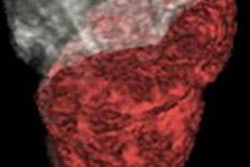

The results are an early confirmation that the imaging technique can show tumors in 3D and accurately measure tumor viability and death, according to a release from Johns Hopkins. In addition, the findings suggest that using the technique before and after treatment is a better way to predict patient survival after chemoembolization.

While standard methods of assessing tumor response are based on 2D images and tumor size, the new technology also distinguishes between dead and living tissue. The 3D technology builds upon 2D methods and uses computer analytics to evaluate the amount of contrast absorbed by tumor tissue: Living tissue will absorb more contrast than dead tissue, the researchers believe.

In the first study of 17 patients, the error margin of the new 3D analysis was less than 10% for predicting the amount of dead tumor tissue versus pathology, compared with as much as 40% with the 2D method. In additional studies of more than 300 liver tumors in 123 patients, standard methods showed slightly less difference in survival between patients who responded to therapy and those who did not, compared with the 3D technique.